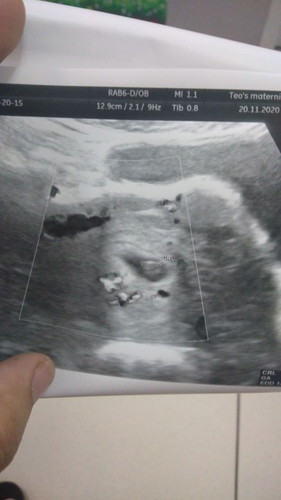

First baby...

6w3day.... Belum Ada bunyi heartbeat baby.. minggu depan scan lagi... Mudah2han.. Ada bunyi minggu depan..... #firstbaby #bantusharing

Kita sama sis. Saya pun 6weeks. Smlm scan takde heartbeat baby lagi. Btw tahniah

saya scan 6week 6hari dah nampak kantung semua jelas n dah dengar hearbeat jugak .